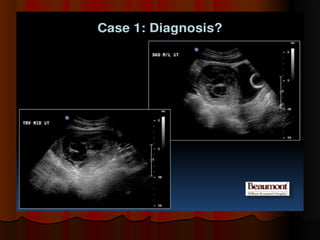

Succenturiate placentaSuccenturiate placenta

This was a 3rd trimester pregnancyThis was a 3rd trimester pregnancy

showing part of the placenta along theshowing part of the placenta along the

anterior wall of the uterus (SUCCENT PL),anterior wall of the uterus (SUCCENT PL),

and the main part of the placenta alongand the main part of the placenta along

the posterior wall (PL).the posterior wall (PL). The sucenturiateThe sucenturiate

lobe of placenta is connected to the mainlobe of placenta is connected to the main

placenta by a string of blood vessels.placenta by a string of blood vessels.